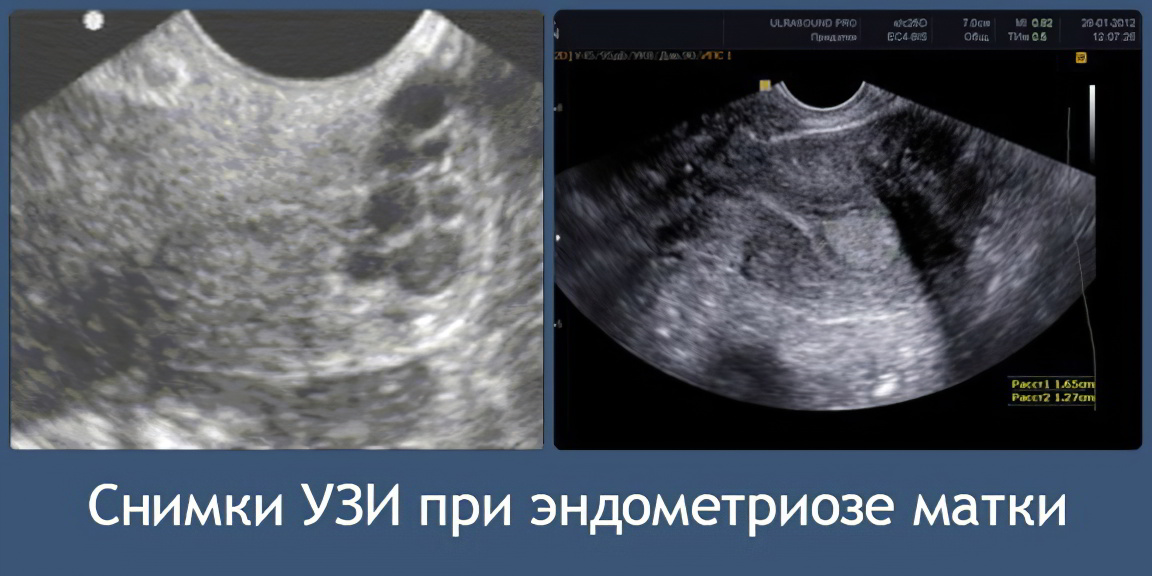

Ультразвуковое исследование позволяет выявить характерные узелки на стенке матки.

1. Ультразвуковое исследование органов малого таза. Признаки, указывающие на эндометриоз:

• Анэхогенные образования диаметром до 6 мм;

• Зоны с повышенной эхогенностью;

• Увеличение размеров матки;

• Полости с жидкостью;

• Узлы с размазанными формами, напоминающими овал (при узловой форме заболевания), достигающие 6 мм в диаметре;

• Мешотчатые образования до 15 мм в диаметре при очаговой форме болезни.